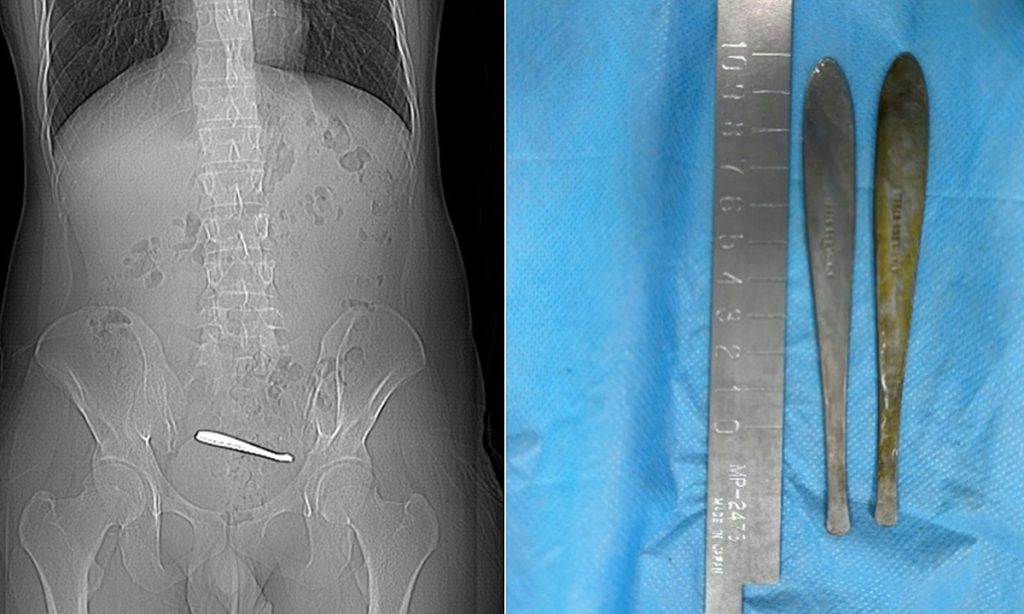

Phim chụp cho thấy dị vật trong ổ bụng bệnh nhân. Ảnh: Khoa Tiêu hóa, Bệnh viện Cổ Lâu Nam Kinh

Kết quả chụp CT tại Bệnh viện Cổ Lâu Nam Kinh phát hiện chiếc thìa đang bị kẹt tại khoang chậu (pelvic cavity). Do dị vật gây tắc nghẽn kéo dài, vùng niêm mạc xung quanh đã xuất hiện tình trạng loét, dẫn đến nguy cơ thủng ruột nếu không được xử lý kịp thời. Các dị vật này có chiều dài khoảng 12 cm, nằm trong phần ruột non vốn có cấu tạo hẹp, khiến việc tiếp cận và loại bỏ gặp nhiều khó khăn. Sau gần một giờ thao tác, các bác sĩ đã sử dụng thiết bị nội soi để gắp thành công cả hai chiếc thìa ra ngoài một cách nguyên vẹn, giúp bệnh nhân tránh được một cuộc phẫu thuật xâm lấn. Sức khỏe của anh Trương đang trong quá trình hồi phục.

Các bác sĩ sử dụng thủ thuật nội soi để gắp dị vật trong bụng bệnh nhân. Ảnh: Khoa Tiêu hóa, Bệnh viện Cổ Lâu Nam Kinh